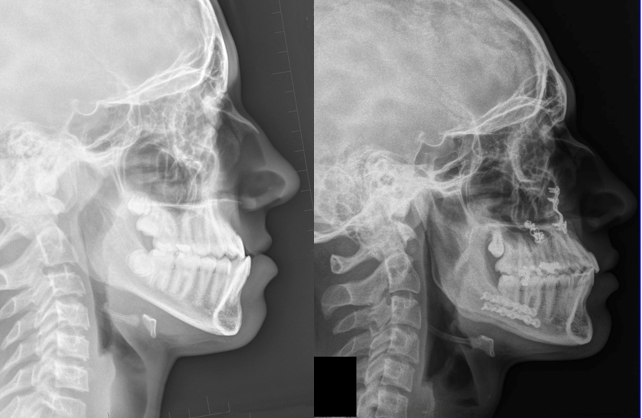

Kombinovaná ortodonticko chirurgická léčba: obrácený skus (chirurgická část terapie ve VFN Praha: prof. MUDr. R. Foltán, Ph.D.)

Začátek, obrácený skus, "podkus", "čelisti koušou obráceně"

Konec po sejmutí fixního aparátu

Boční dálkový snímek lbi před léčbou a po jejím skončení